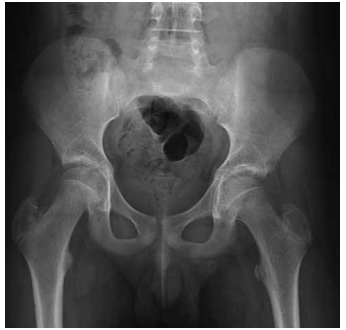

Paciente de 15 anos, sexo masculino, IMC = 38

kg/m2, vem apresentando dor na coxa e região

púbica a esquerda há 4 semanas e queixa de claudicação intermitente. Nega trauma e não refere a

prática de atividades físicas. Foi encaminhado ao

ortopedista que solicitou exame radiográfico.

Considerando o quadro clínico e o exame radiográfico, pode-se afirmar que: